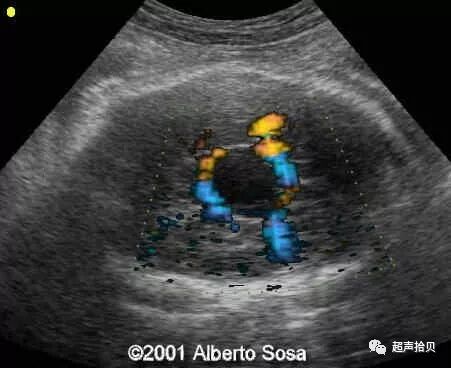

图1:横向声像图显示位于中线蛛网膜囊肿(C), 彩色多普勒没有血流显示;